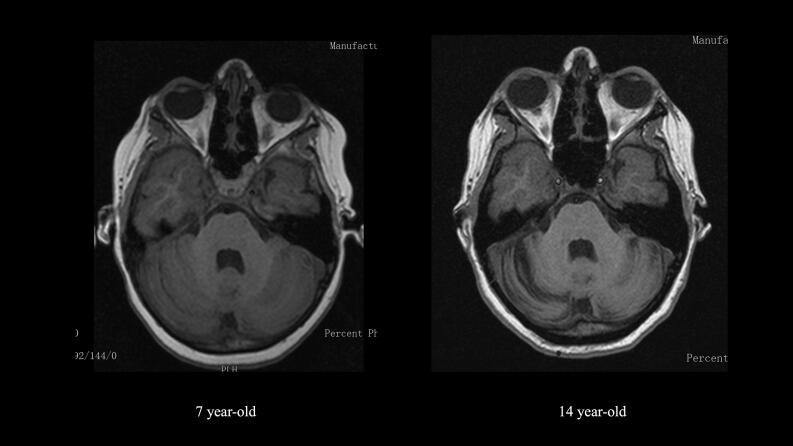

Fig. 1.

Brain MRI of the patient at 7 years (left) and 14 years (right) - T1 weighted, axial view at cerebellum level showing cerebellar hemispheric mild atrophy at 14 years of age.